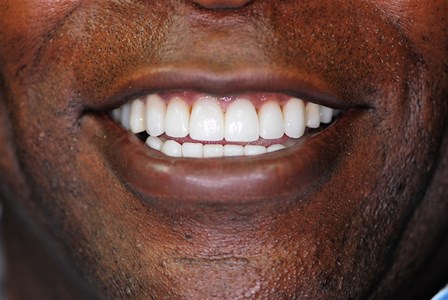

Before

After